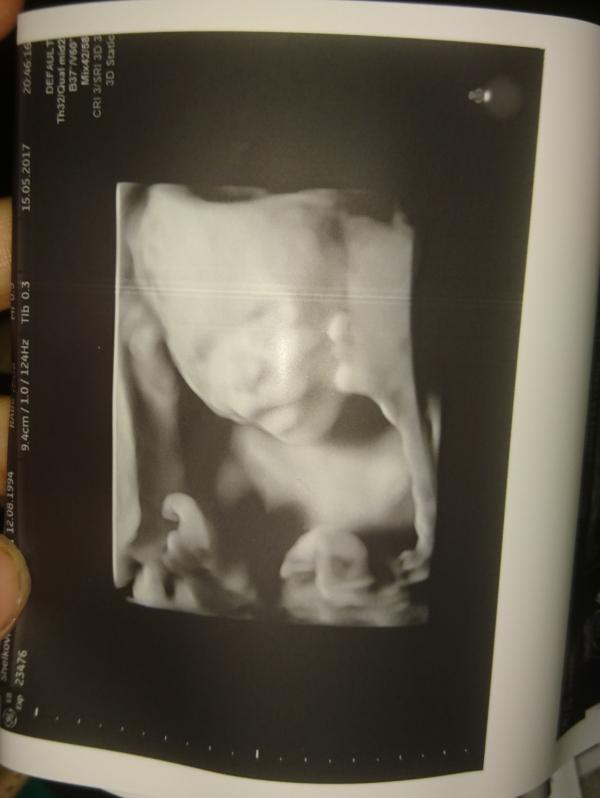

Эволюция моей принцессы из горошинки в человечка) МОИ УЗИ смотрю и вспоминаю эти волнительные походы к врачу )